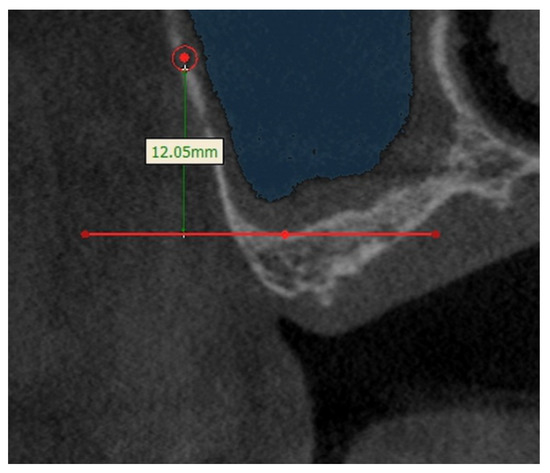

3.1. The Height of the Posterior Superior Alveolar Artery (PSAA)

| Height from the Sinus Floor | |||

| Mean ± S.D. | Maximum | Minimum | |

| Height (mm) | 11.91 ± 4.79 | 24.05 | 3.03 |

| (Mean ± S.D.) | |||

| Gender | p-Value | ||

| Male | Female | ||

| Height (mm) | 11.94 ± 5.08 | 11.87 ± 4.40 | 0.952 |